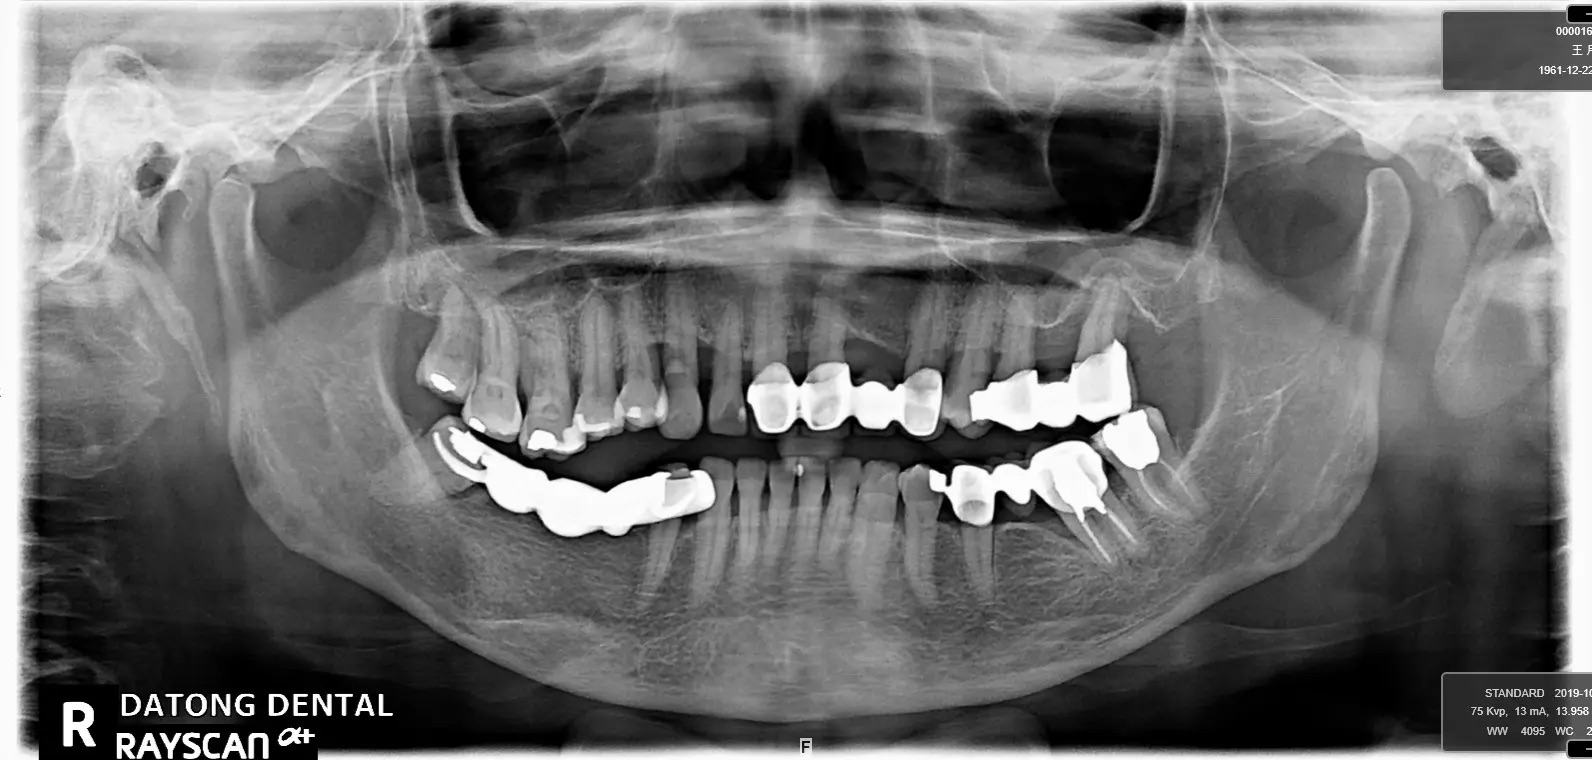

植牙成功案例